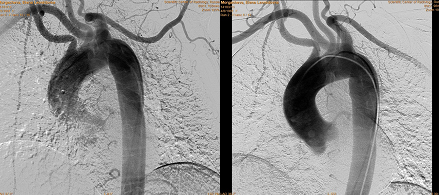

В послеоперационном периоде больная была дополнительно обследована: выполнена компьютерная томография шеи и органов грудной клетки с ангиографией (рис. 3 а, б) и прямая ангиография (рис. 4), по данным которых подтверждено наличие у пациентки аномалии развития ветвей аорты. Правая подключичная артерия отходит от уровня перешейка аорты по ее задней поверхности самостоятельным стволом, проходя между аортой и позвоночным столбом на уровне третьего позвонка, – a. lusoria. От правой подключичной артерии отходит правая позвоночная артерия. Правая общая сонная артерия отходила от аорты одним устьем вместе с левой общей сонной артерией, что наглядно демонстрируется на ангиограммах в виде симптома “бычьих рогов”. Послеоперационный период у больной протекал гладко, без осложнений. Фонация голосовых связок не была изменена.

Рис. 3. Результаты компьютерной томографии шеи и органов грудной клетки с ангиографией: а – аорта (вид сзади); б – предпозвоночное расположение правой подключичной артерии.

Рис. 4. Ангиография (селективное контрастирование сонных, левой и правой подключичных артерий).